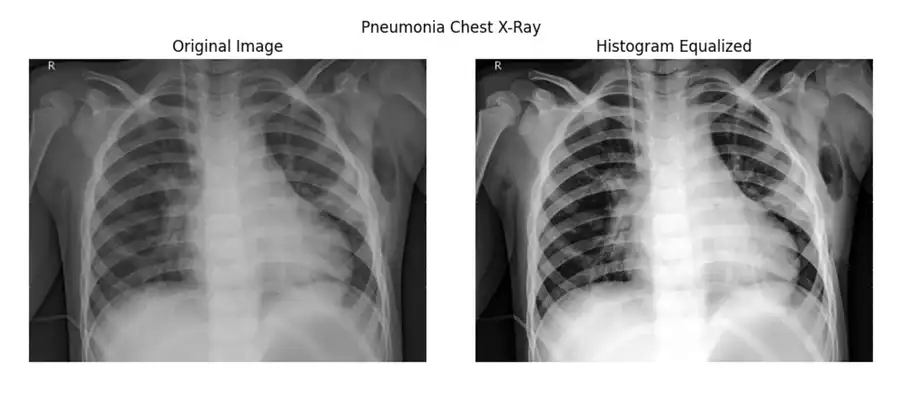

Progressive CNN Architecture for Pneumonia Detection

A Deep Learning Pneumonia Detection System employing a progressive CNN architecture for chest X-ray analysis. This framework leverages three approaches: a basic CNN, an enhanced architectural model, and a histogram-equalized variant, focusing on binary classification optimization through systematic experimentation and preprocessing techniques.